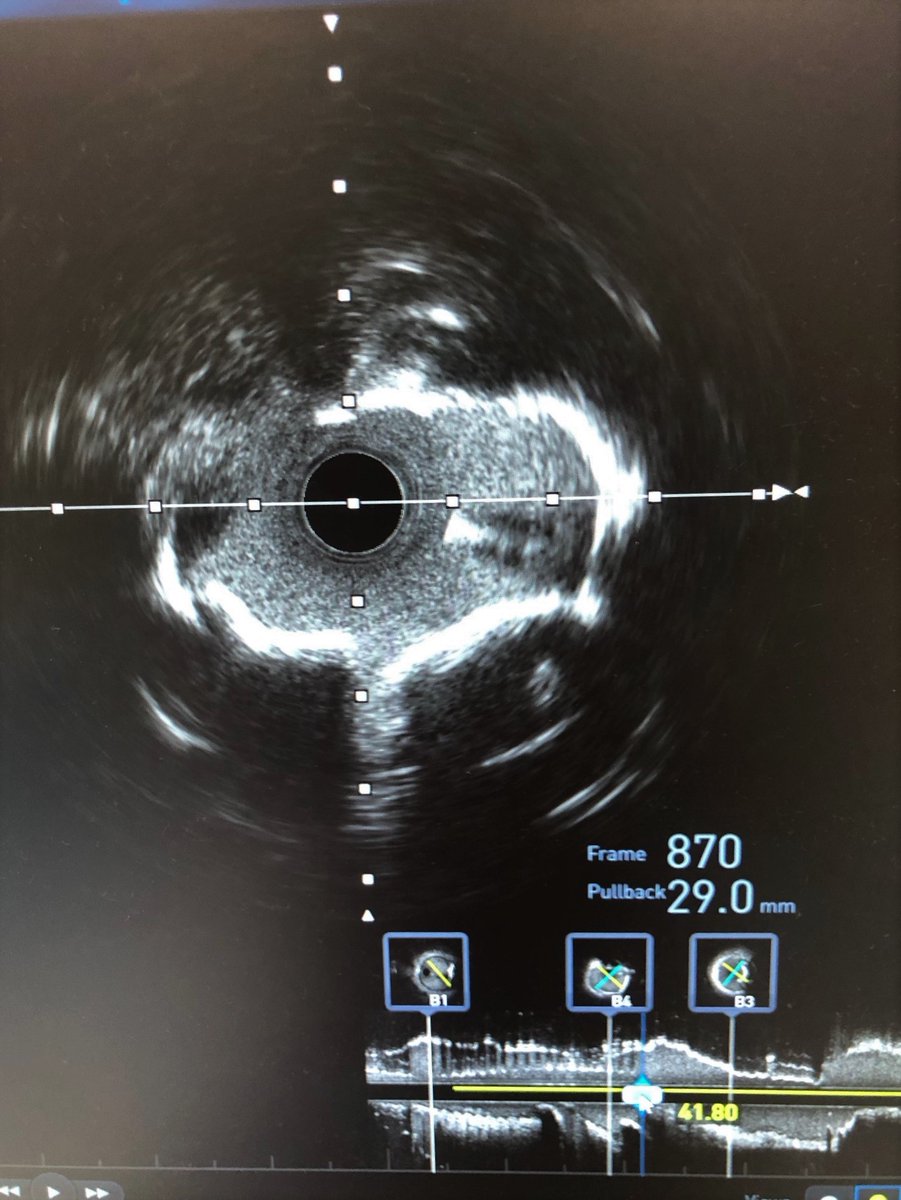

Check out the before and after images of this HD #IVUS guided #RotaShock PCI to optimize deployment of a 3.00x38mm SYNERGY XD. Congrats to @DoctorMoussa of @VirtuaHealth on successfully opening this heavily calcified LAD, making for a great #ComplexPCI case!

BSCCardiology's tweet image. Check out the before and after images of this HD #IVUS guided #RotaShock PCI to optimize deployment of a 3.00x38mm SYNERGY XD. Congrats to @DoctorMoussa of @VirtuaHealth on successfully opening this heavily calcified LAD, making for a great #ComplexPCI case!